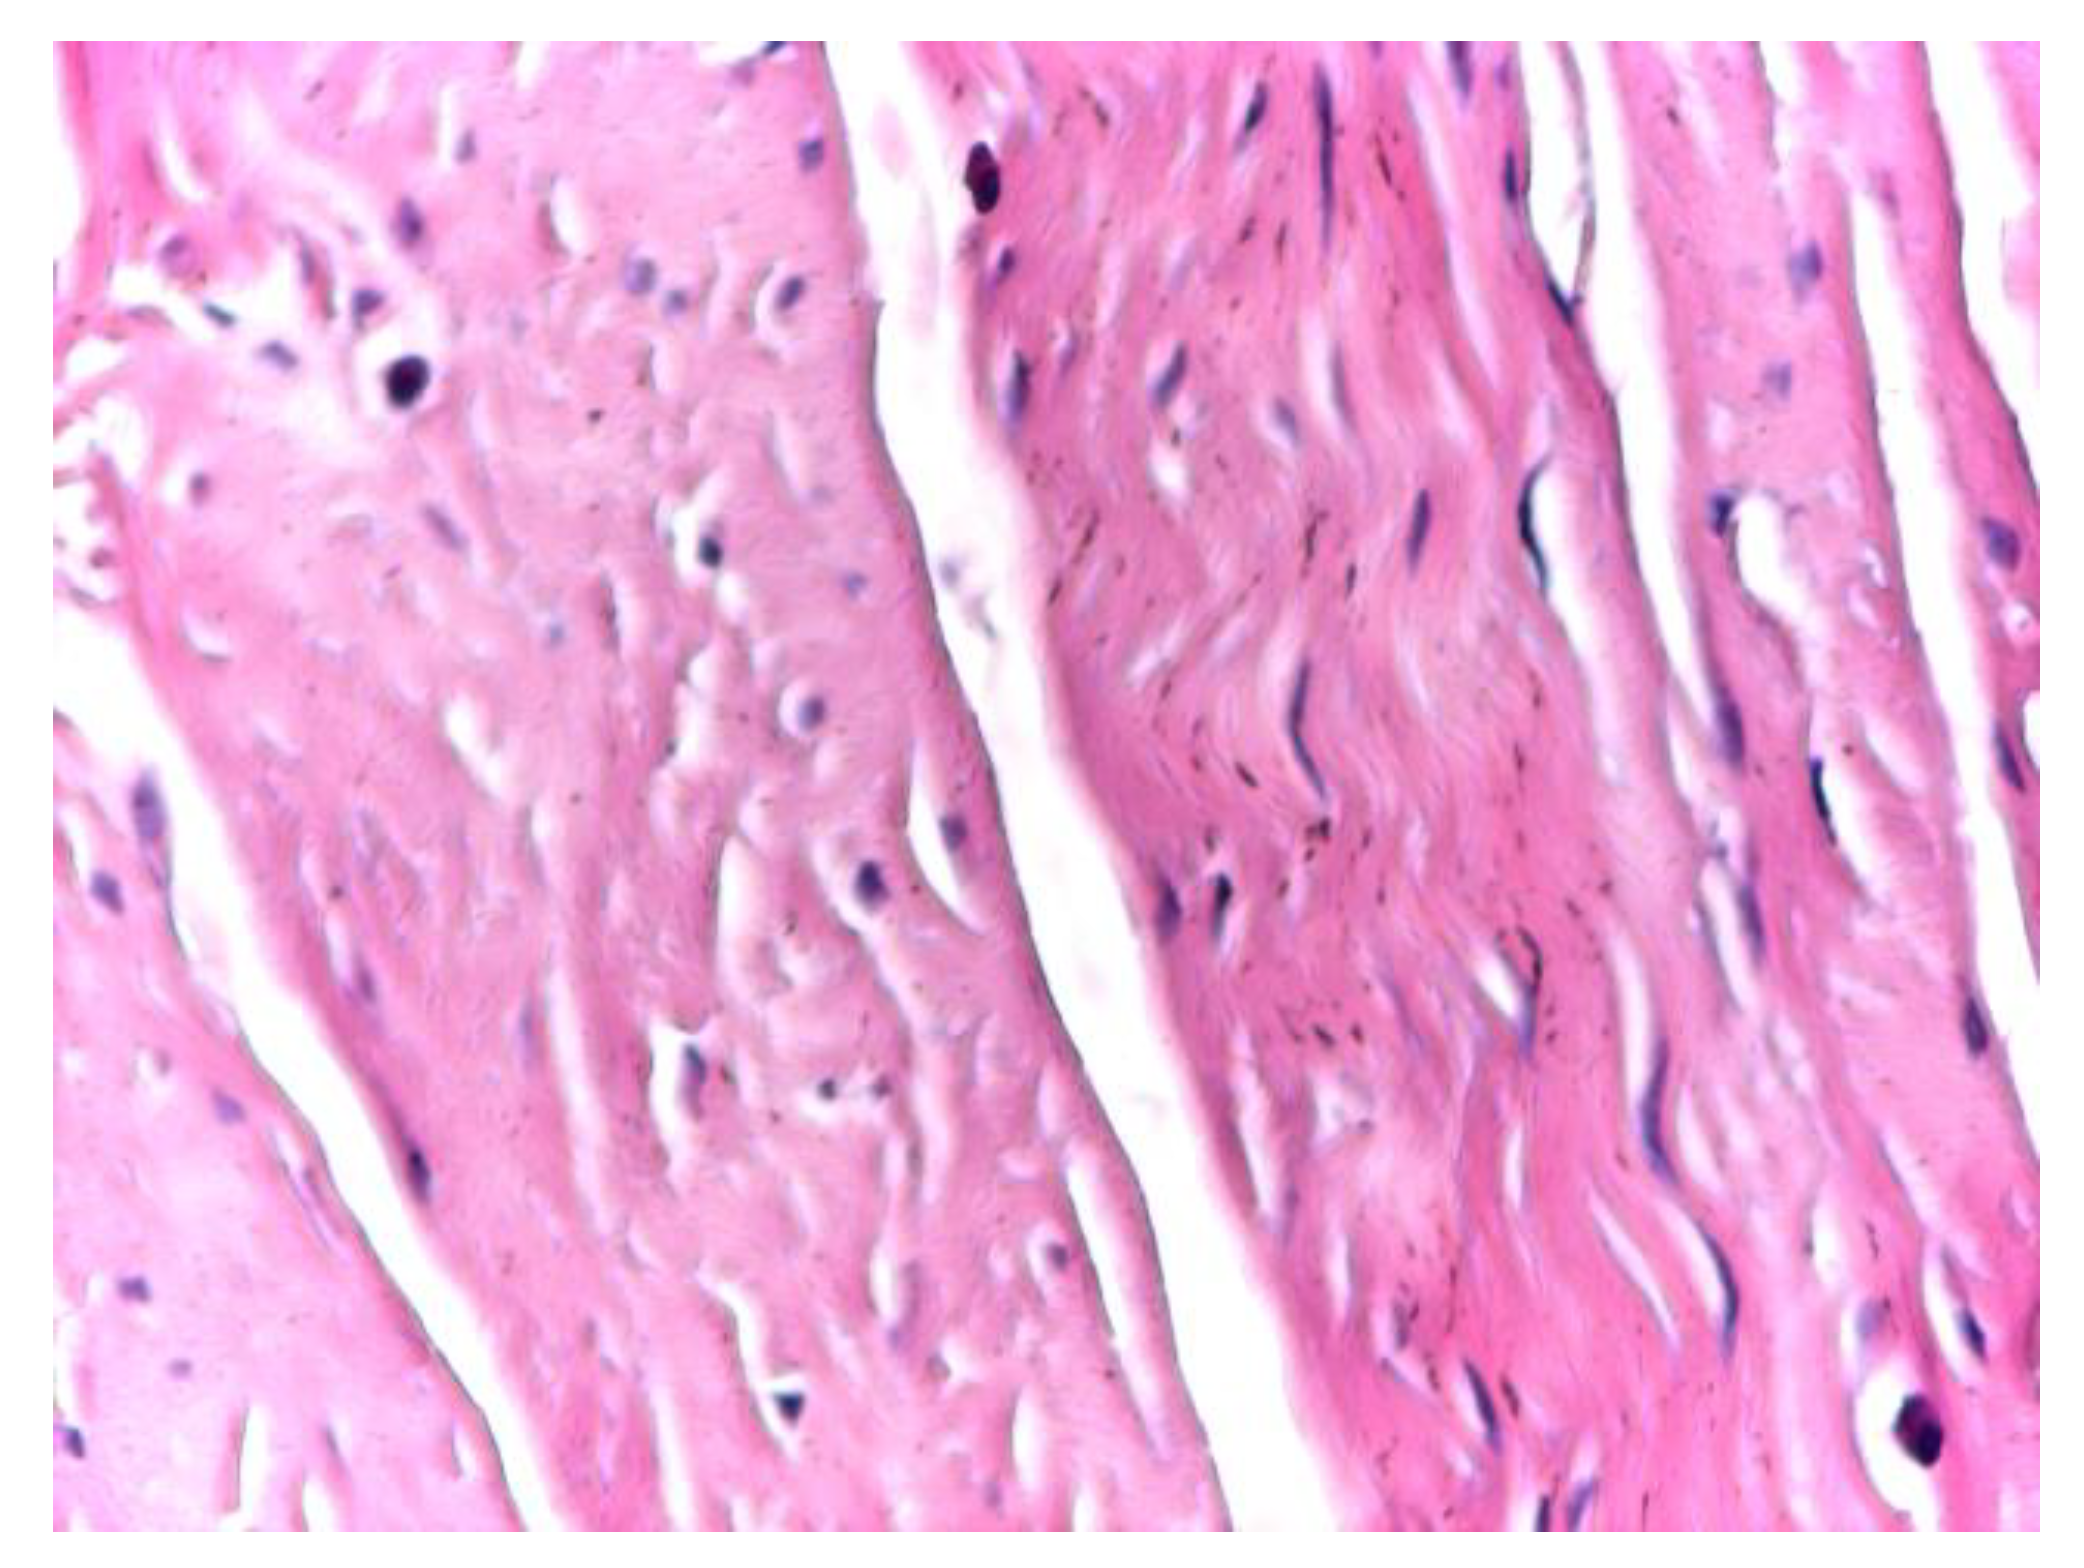

At intermediate magnification (×10), the aponeurotic tissue exhibited a sparse cellular component embedded within the collagen matrix, consisting predominantly of fibrocytes with occasional elongated fibroblasts. The collagen bundles maintained a uniform and parallel arrangement, without evidence of structural disruption or pathological remodeling (Figure 2).

Figure 2. Optical microscopy of human aponeurotic tissue showing predominantly fibrocytes with sparse elongated fibroblasts within an organized collagenous matrix. Hematoxylin and eosin staining (H&E); original magnification ×10.